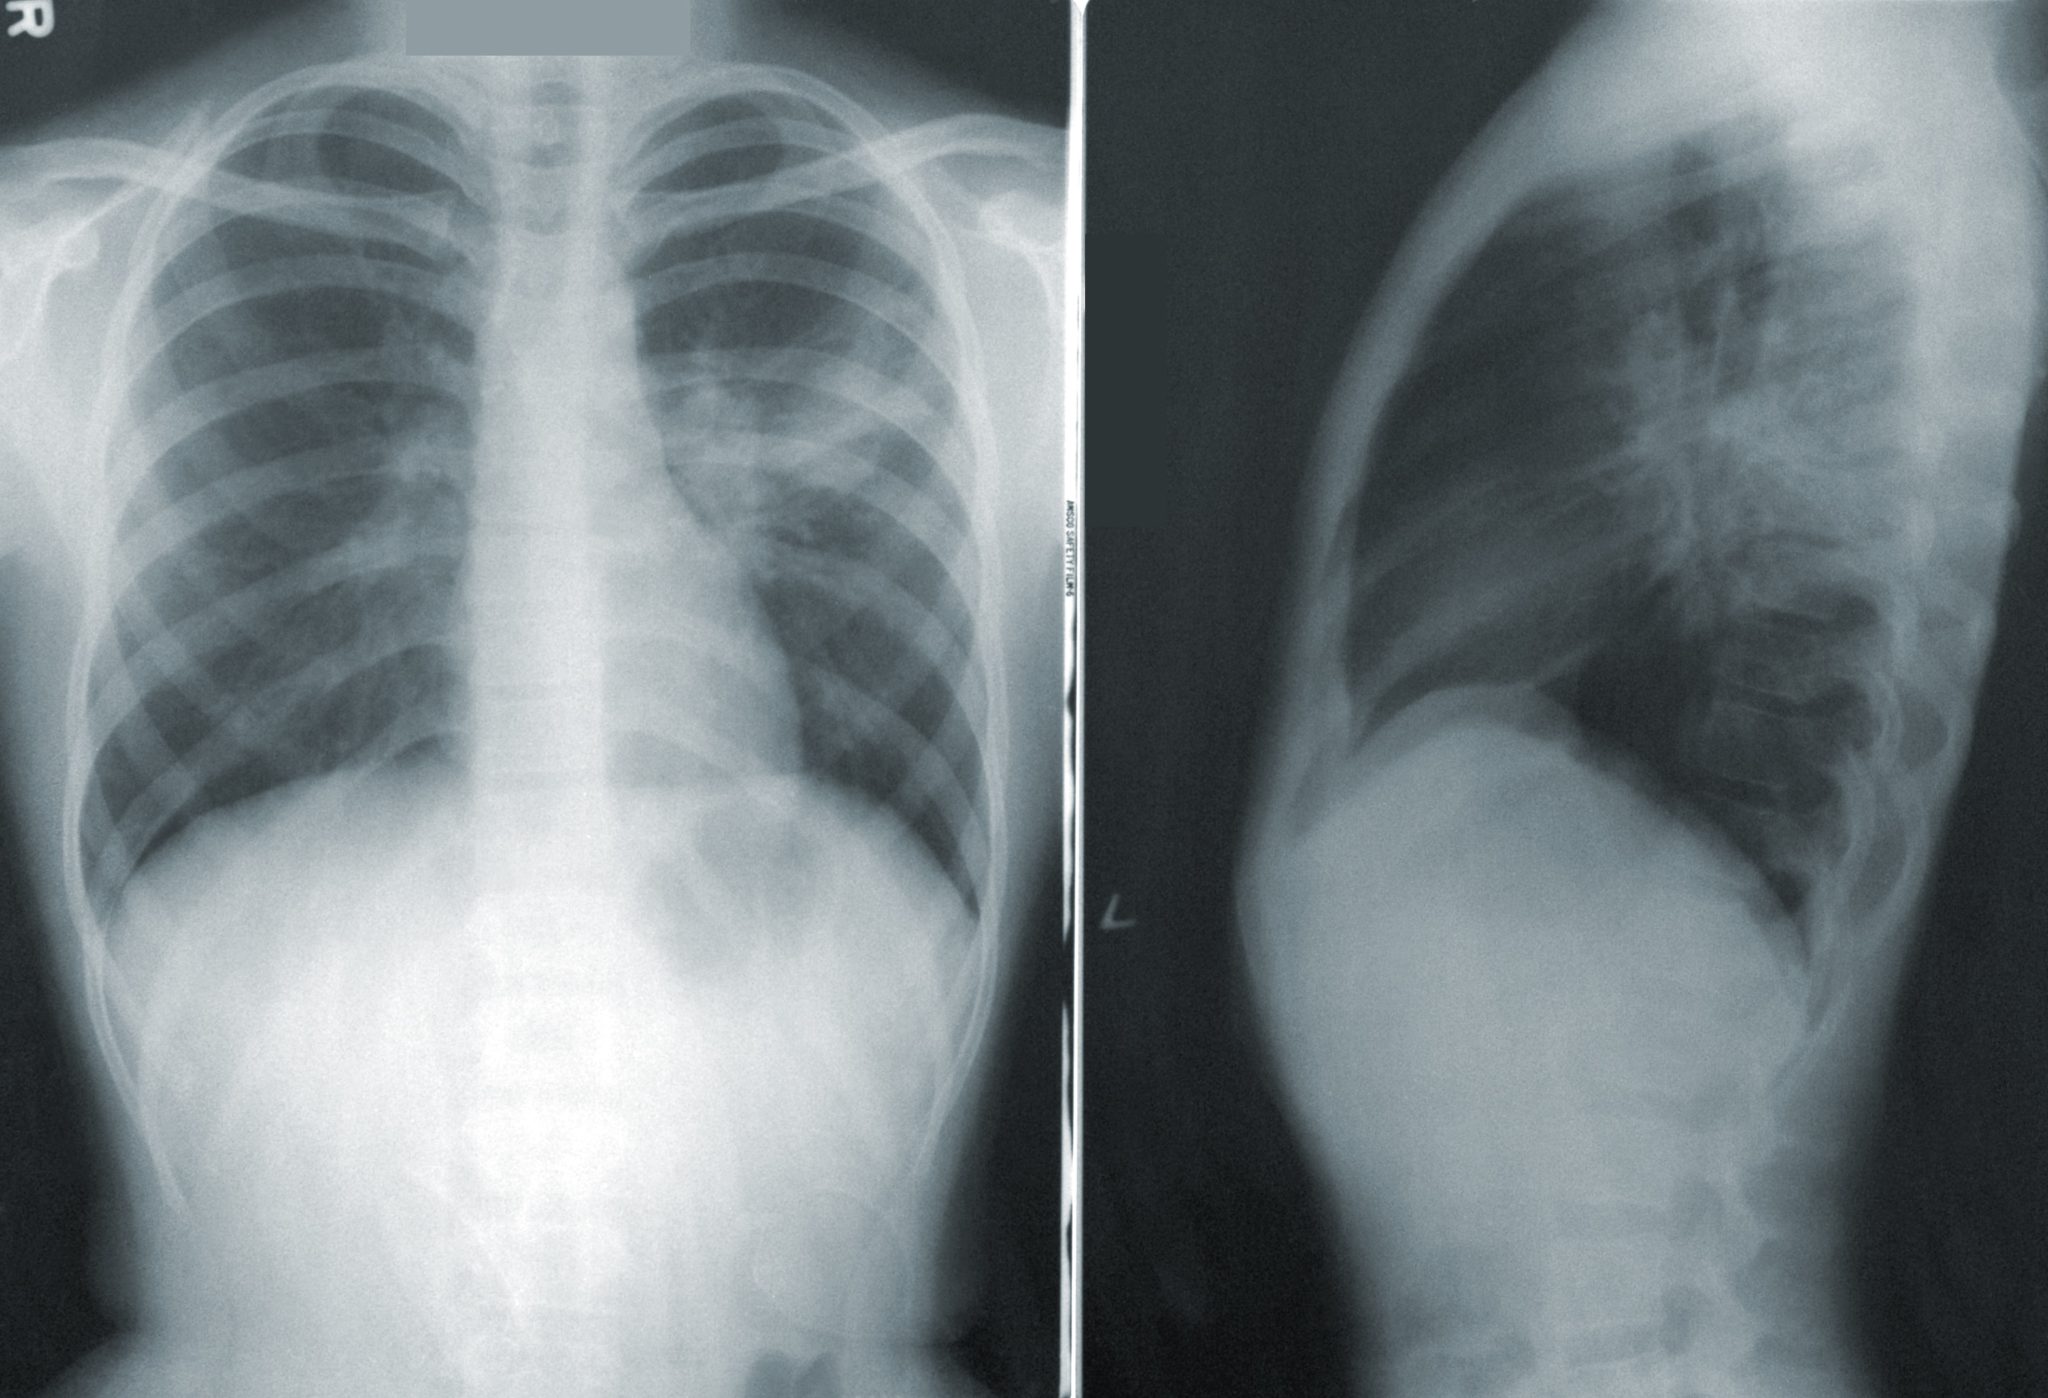

«Ένας ταχυδρόμος από το Πρέστον της Αγγλίας, εισέπνευσε ένα εξάρτημα από Playmobil ως παιδί, αλλά ανακαλύφθηκε μόνο όταν ο 47χρονος έκανε ακτινογραφία στους πνεύμονες όταν παρουσίασε επίμονο βήχα», είπε ο Τέιλορ. «Ενώ δεν υπήρχε για 40 χρόνια ως εύρημα, ένας άνδρας εισέπνευσε ένα μπιζέλι, το οποίο βρισκόταν στη θέση του για αρκετό καιρό ώστε να αρχίσει να φυτρώνει στην αναπνευστική του οδό».